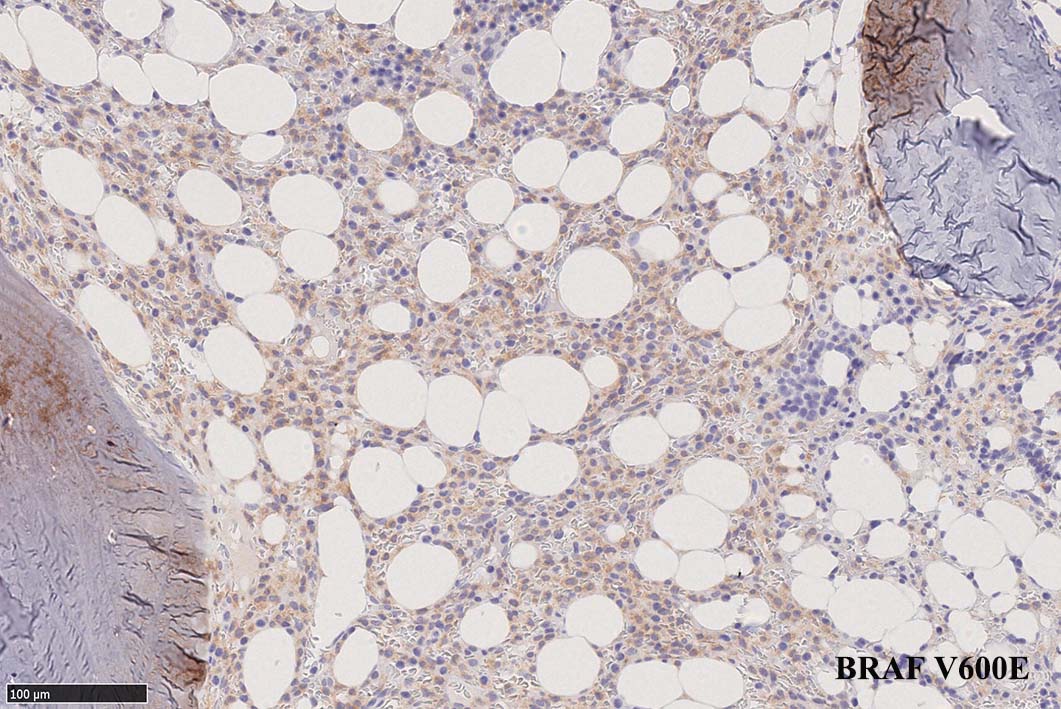

BRAF V600E変異タンパクの免疫染色(山梨医大 大石先生に染色していただきました. ベンタナ, Optiview)

増殖細胞はCD20(相変わらずべったり染まる), CD19, PAX5陽性 CD25陽性.

Pathological Diagnosis: Hariy cell leukaemia